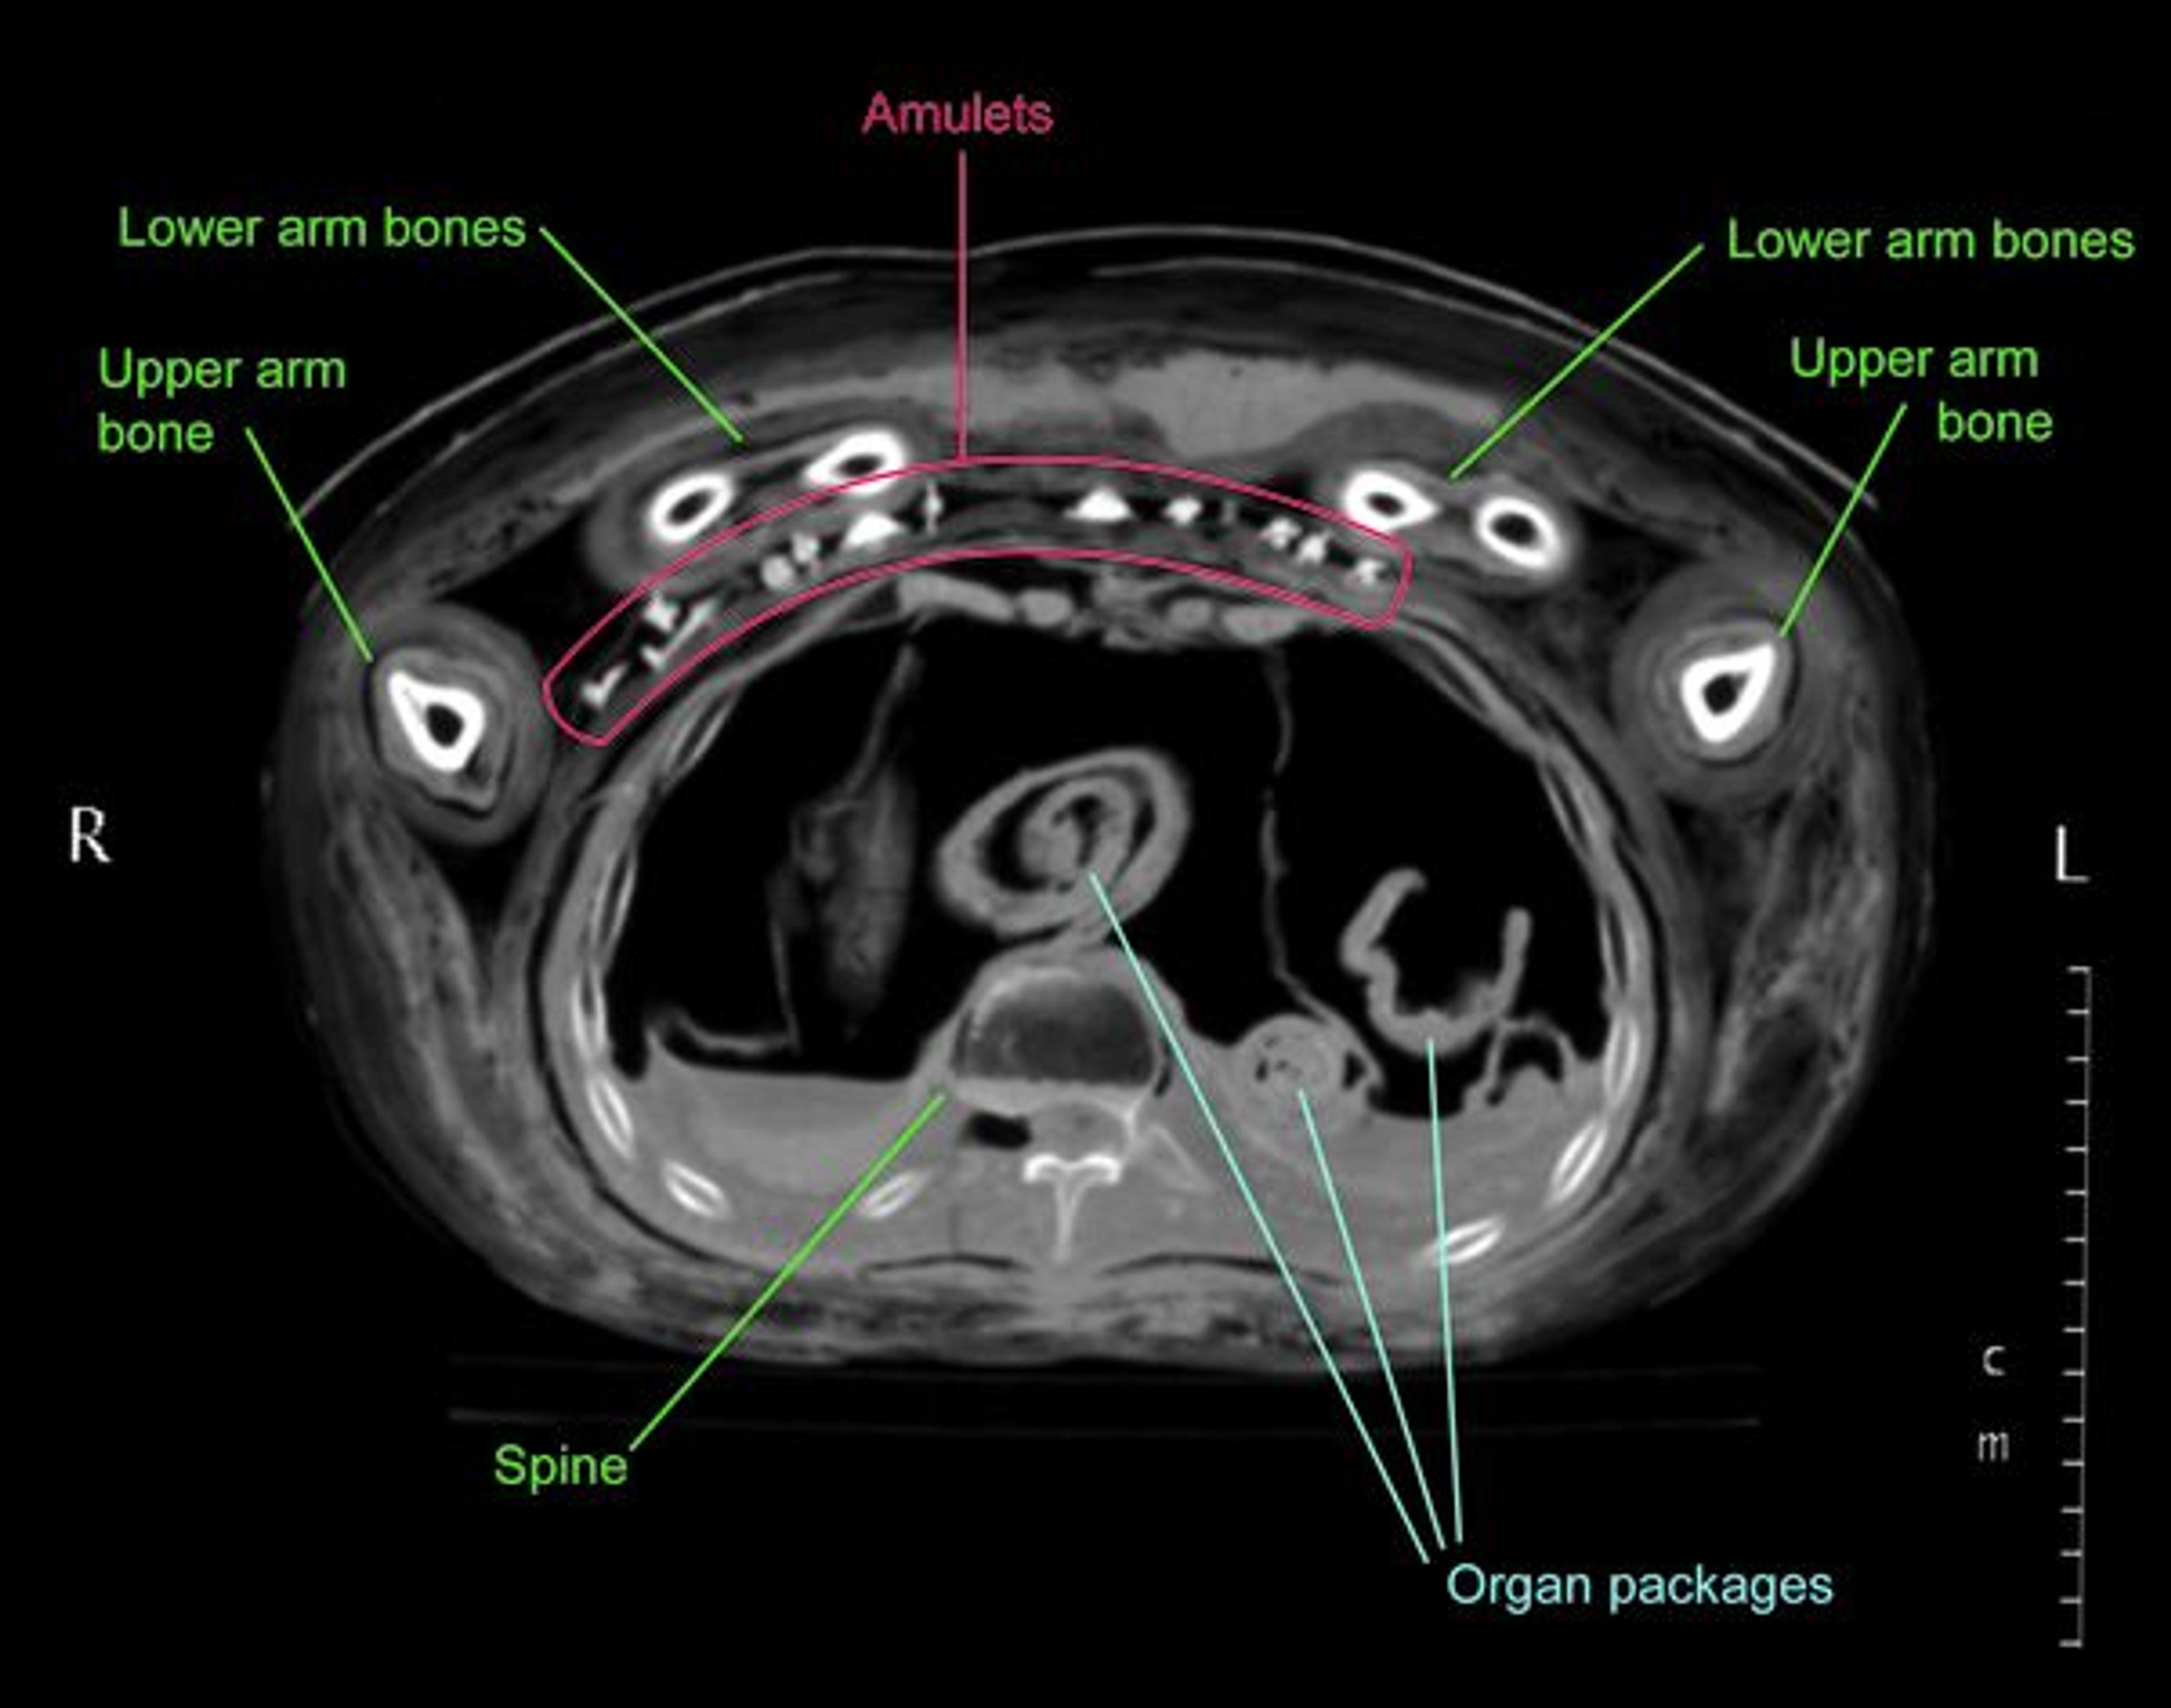

Older X-rays and CT scans of Nesmin that were taken in 1995 and 1997 (figs. 7–8, 10, and 13)2 had shown that his mummy is accompanied by a very large set of amulets (thirty-one in total) within the wrappings. The images that were produced at the time were on film and allowed the identification of the types of amulets (such as a standing god), but the information from these old images was limited and the visible details were not sufficient to permit the identification of the particular gods included, for example.

Medical imaging technology and software have advanced so much over the last fifteen years that new reconstructions from the 2011 CT scan data show Nesmin's body and these small amulets (about 1–1 1/2 in.) with astonishing clarity (see figs. 11–12, and especially 14 and 16).

Radiographic analysis can not only detect objects within the wrappings, but it can also provide information about mummification techniques or the health of an individual. In Nesmin's case we can, for example, see that most of his organs were removed, mummified separately, and then placed back into the chest and stomach cavity (see fig. 8); this was a common practice in the Ptolemaic Period. Images of his hips revealed that he suffered from arthritis.3